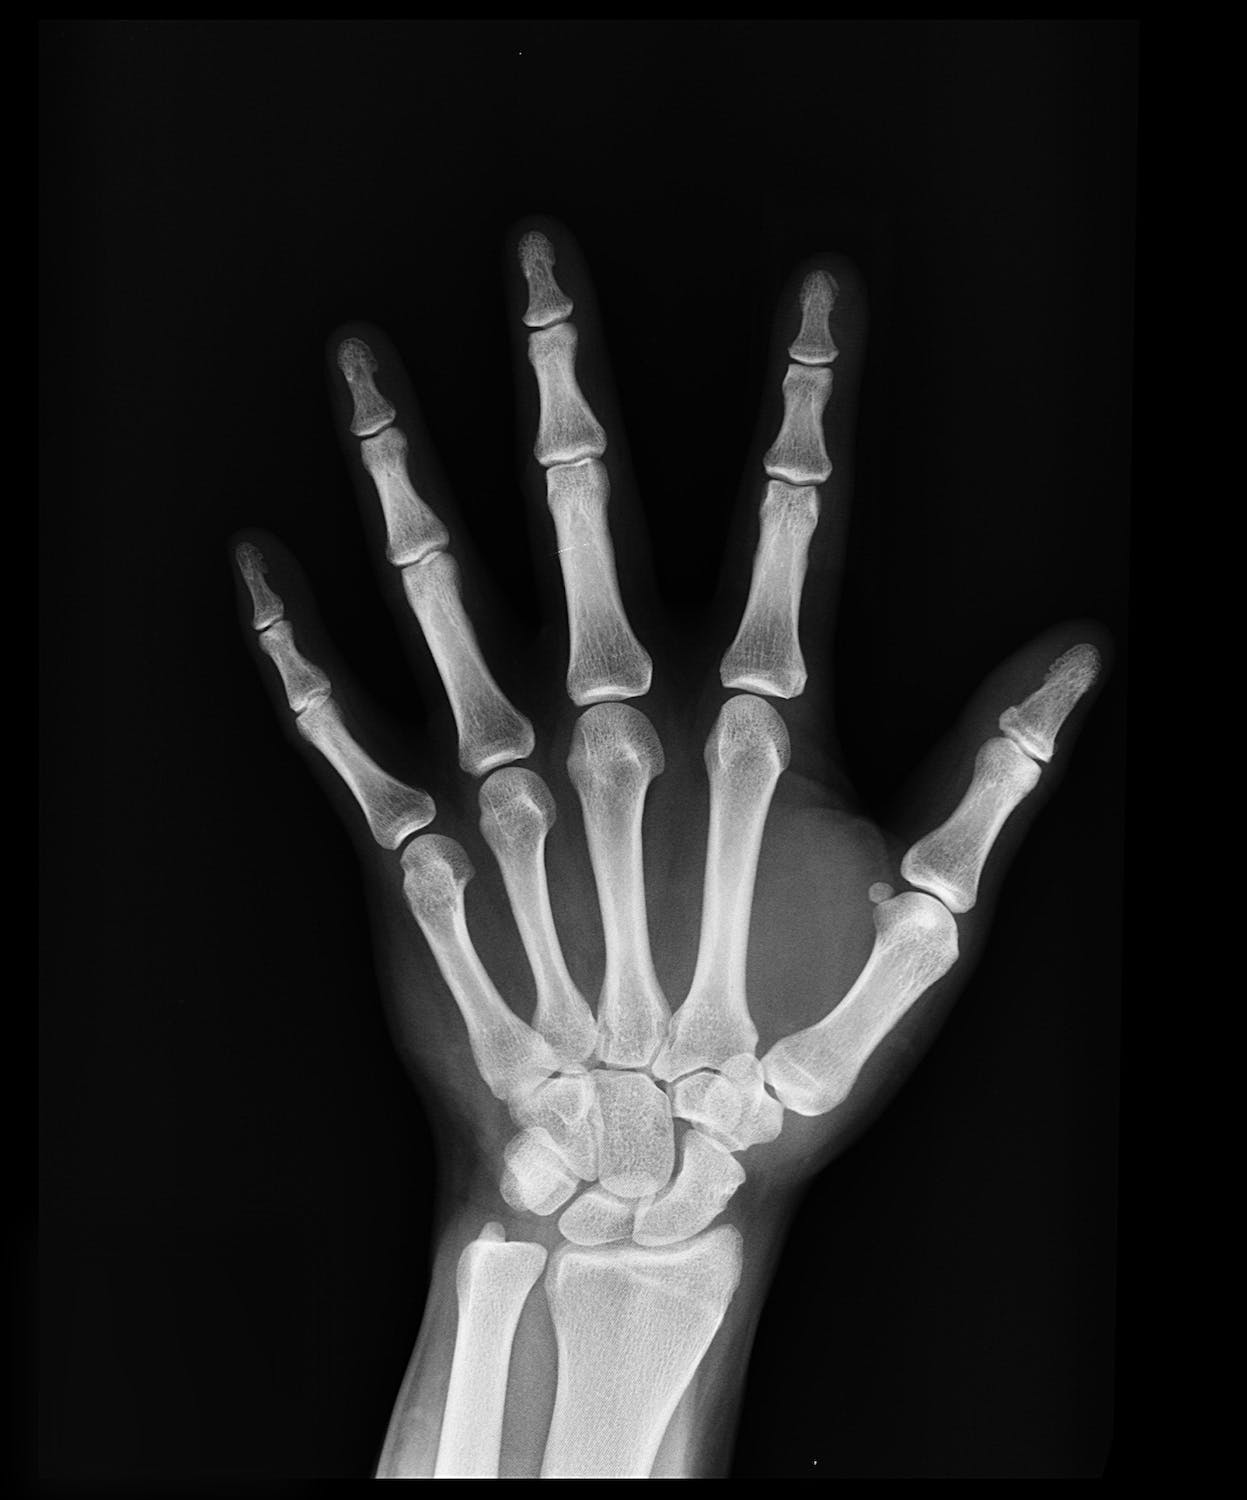

뼈의 강도가 약해져서 골절이 일어날 가능성이 높은 상태로 골다공이란 뼛속에 구멍이 많이 생긴다는 뜻이며, 골다공증은 뼈의 대표적인 미네랄인 칼슘과 인이 감소함에 따라 뼈의 양이 줄어들어 뼈가 얇아지고 약해져 잘 부러지는 질환을 의미합니다.

50~70세 여성의 골절은 주로 손목에서 먼저 발생하는 경우가 많으며 70대 환자들의 경우 고관절 및 척추의 골절이 흔하게 발생하게 됩니다.

4. 골다공증 검사

1) DEXA 스캔 (이중 에너지 X선 흡수골밀도측정법)

DEXA 스캔은 골다공증 검사 중 가장 일반적인 방법 중 하나입니다.

이 기술은 뼈의 밀도를 정확하게 측정하여 골다공증의 위험을 평가하게 되며 저량의 X선을 사용하여 골 조직과 주변 조직의 흡수량을 측정하므로 뼈의 건강 상태를 신속하게 확인할 수 있습니다.